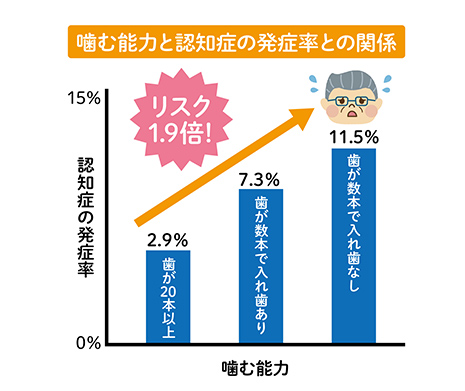

食べ物をよく噛むことは、脳を刺激するため認知症との関連性があると考えられています。ご自身に合わない入れ歯を使用し、柔らかい食べ物ばかりで普段からあまり噛まない食事をしていると、認知症が進んでいくというデータが出ています。